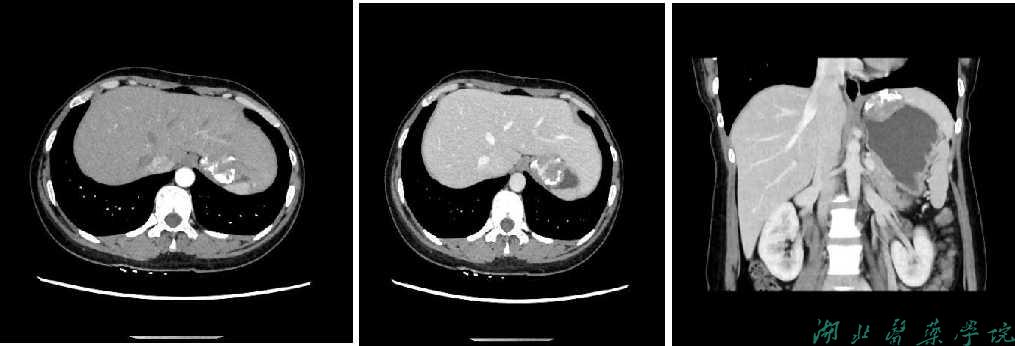

上腹部增强CT示:肝胃间隙内见团块状软组织密度灶,边界尚清,大小约4.1×3.5×3.2cm,病灶内见较多斑片状、环状钙化,增强病灶实性部分呈不均匀渐进性强化,邻近胃壁受压内陷,与邻近肝实质分界欠清诊断:肝胃间隙肿瘤性病变,胃来源?胃间质瘤可能。胃镜下表现为粘膜充血、水肿,散在出血点,诊断为慢性浅表性胃炎。

图1 a)腹部CT增强动脉期;b)门静脉期;c)门静脉期冠状位;d)门静脉期矢状位,可见肝胃间隙软组织密度肿块,肿块边缘钙化,增强呈不均匀渐进性强化。